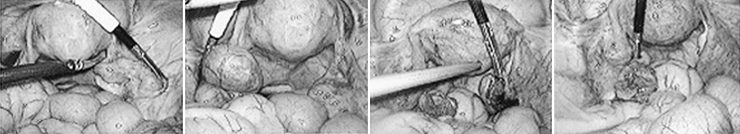

• 자궁근종절제술

자궁근종의 위치에 따라 근종에 의한 자궁각부분의 폐쇄나 비정상적인 자궁 수축에 의해 난자나 정자의 이동 및 배아의 착상을 방해함으로써 난임의 원인이 될 수 있습니다. 하지만 자궁근종의 크기가 너무 크거나 개수가 많은 경우엔 개복 수술을 시행할 수 있습니다.